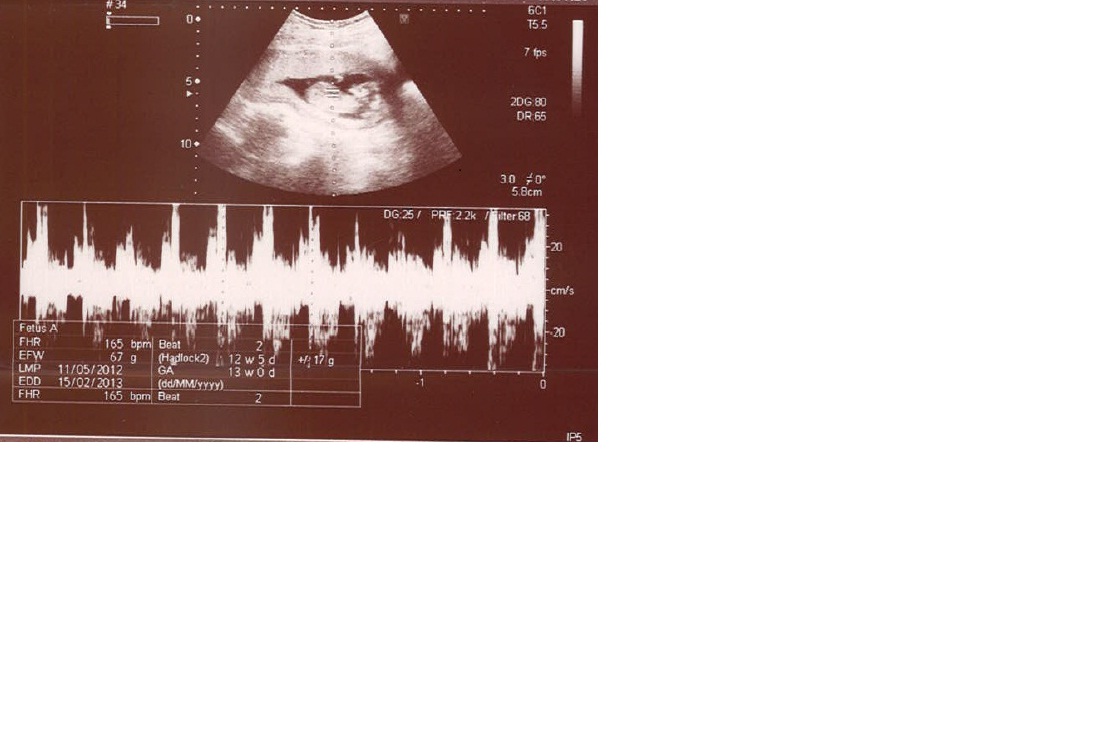

these are my 21 week scan pics... if u could tell from them... but they are even not more clear :( really want to know what i am carrying :(